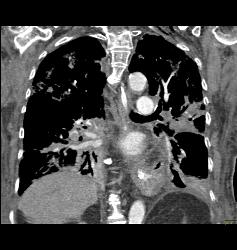

GSW With Bullet in Heart